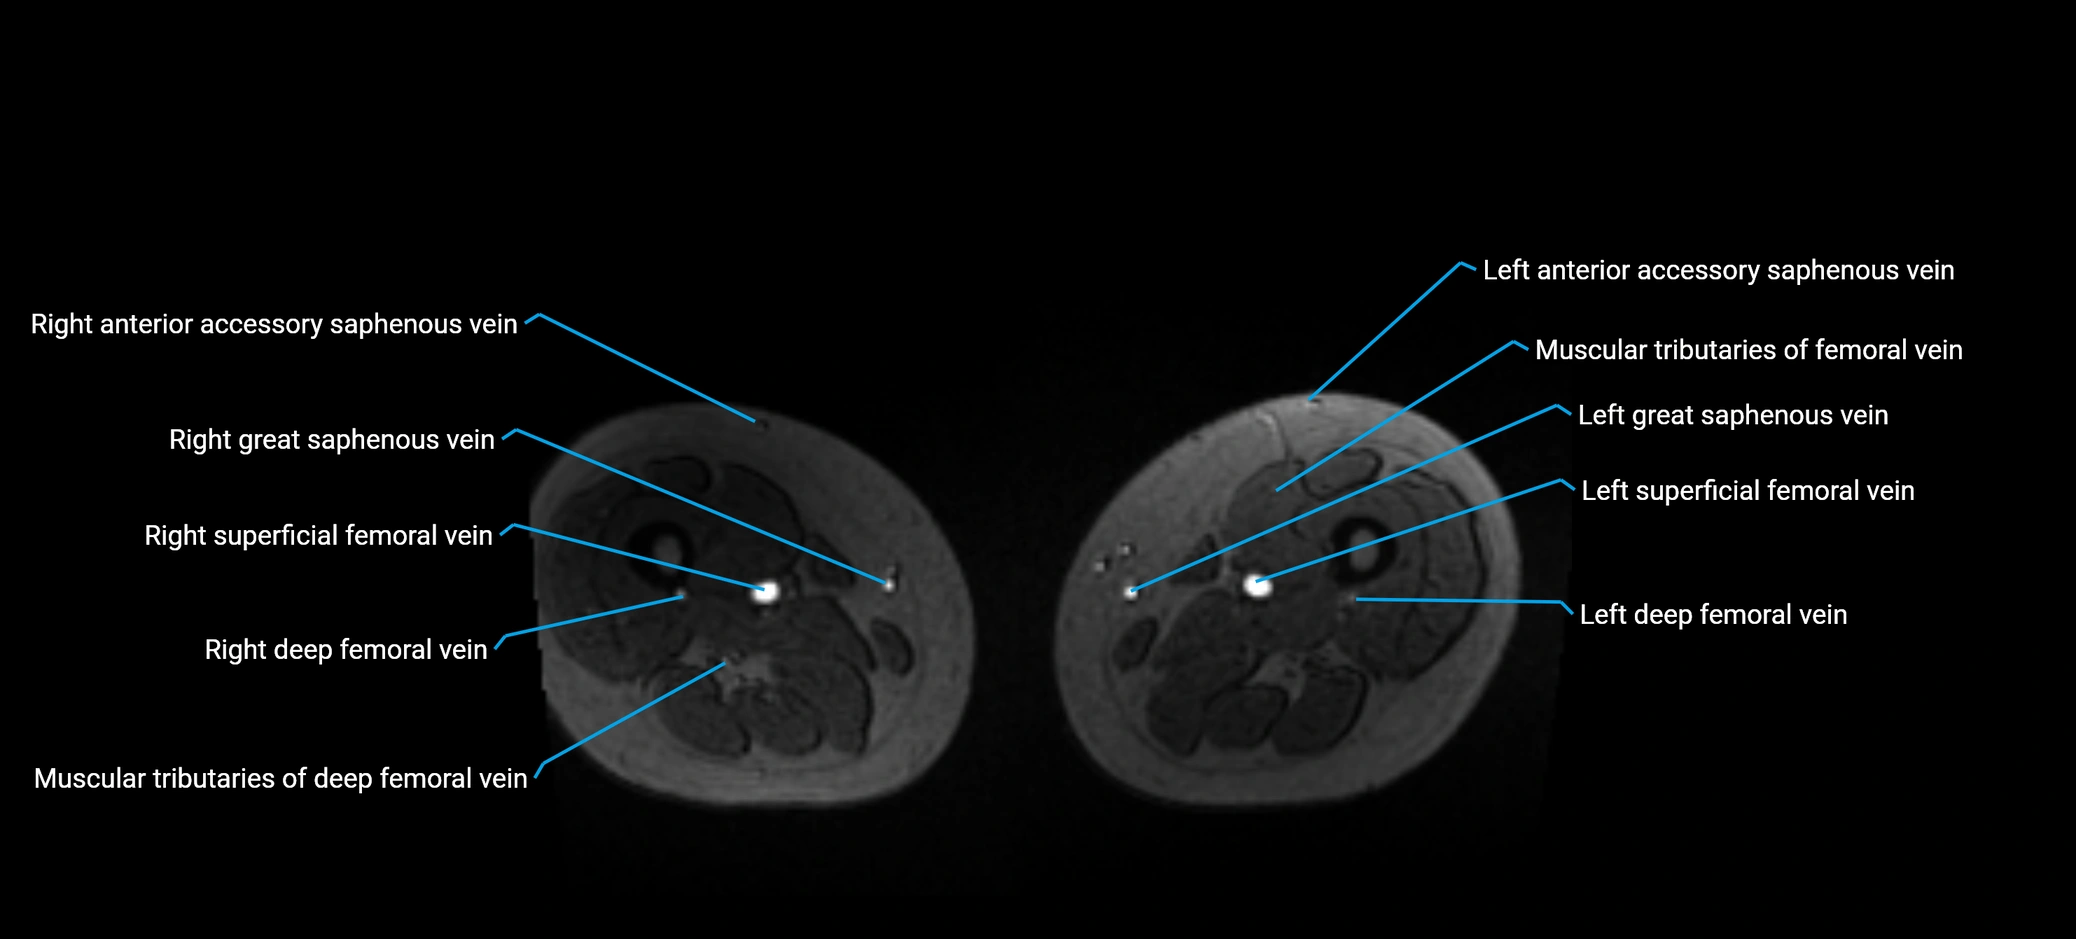

MRI image

image